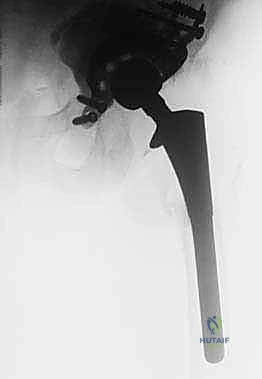

2. النهج الجراحي (Surgical Approach)

للوصول إلى المفصل وتوفير رؤية واسعة، يستخدم الدكتور هطيف عادة النهج الخلفي (Posterior Approach) أو النهج الجانبي الموسع. في بعض الحالات التي يكون فيها استخراج ساق الفخذ القديمة صعباً جداً، قد يلجأ إلى تقنية متقدمة تُسمى "قطع المدور الأكبر الممتد" (Extended Trochanteric Osteotomy - ETO)، حيث يتم فتح عظم الفخذ طولياً كالكتاب لاستخراج الساق بأمان دون كسر العظم، ثم يعاد إغلاقه وربطه بأسلاك معدنية قوية.

5. الترقيع العظمي المكثف (Impaction Bone Grafting)

لتعويض العظم المفقود وملء الفجوات الكبيرة، يتم استخدام كميات هائلة من العظم. يتم طحن العظم (سواء من متبرع أو عظم صناعي) إلى قطع صغيرة، ثم يتم دكه وضغطه بقوة شديدة داخل العيوب العظمية في الحوض باستخدام أدوات طرق خاصة (Impactors). هذه الطبقة من العظم المدكوك ستشكل الأساس الذي سيستقر عليه القف